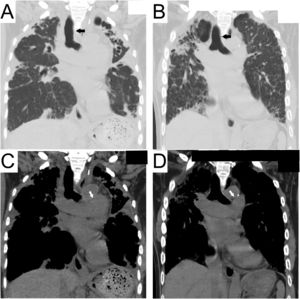

Among 4299 cases of “interstitial pneumonia” or “pulmonary fibrosis,” 20 cases included “vocal cord palsy,” “recurrent nerve palsy,” or “hoarseness” (Supplemental Figure). After excluding the involvement of lung cancer, post-operation, no interstitial lung disease (inappropriate disease name), and insufficient data, four cases were finally identified. In addition to two previously reported cases of idiopathic PPFE,1,2 one case of idiopathic PPFE with usual interstitial pneumonia (case #1; Table 1) and one case of PPFE secondary to fibrotic hypersensitivity pneumonitis (fHP) (case #2; Table 1) were newly identified. The following findings were also common to the previous two cases: Left-sided VCP, radiological PPFE,3 particularly rightward deviation of the trachea caused by fibrosis and contraction of the upper lobe (Fig. 1), and complication of pneumonia.

Chest computed tomography scan at the onset of vocal cord palsy. Coronal view of the tracheal bifurcation level. Pulmonary (A) and mediastinal (C) windows in Case #1 and Case #2 (B, D). Rightward deviation of the trachea (black arrows) caused by fibrosis and contraction of the upper lobe is shown (A, B). The aortic arch and pulmonary artery are in close contact (white arrows) with the tracheobronchial and mediastinal deviations (C, D).

A rightward deviation of the trachea by contraction of the upper lobe was observed (Fig. 1) because the trachea could easily deviate to the right side due to the presence of the aorta and other structures on the left side of the mediastinum. The palsy manifested on the left side opposite the tracheal deviation toward the right, thereby indicating the first and/or second mechanism above. In addition, in cases #1 and #2, PA enlargement secondary to PH could have affected the palsy by further compressing the nerve around the aortic window. To the best of our knowledge, there has only been one report of VCP associated with secondary PH,4 although Ortner syndrome is known to be caused by PA enlargement due to primary PH or aortic arch aneurysms. Secondary PH is usually milder than primary PH and therefore has less impact on VCP; secondary PH alone is not likely to cause VCP.